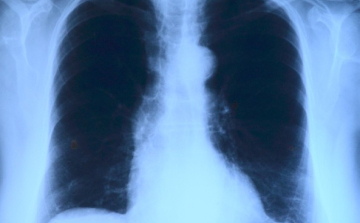

Elvégezték az országban az első tüdőverőér-tágítást

2017. Július 19. 05:01, szerda | Belföld

Az országban elsőként a Debreceni Egyetem Klinikai Központjában végeztek tüdőverőér-tágítást - közölte a felsőoktatási intézmény sajtóirodája kedden az MTI-vel.

Már a 26. tüdőátültetést végezték el Magyarországon

2017. Április 03. 10:20, hétfő | Belföld

A 26. tüdőátültetést végezték el Magyarországon a közelmúltban - közölte az Országos Onkológiai Intézet és a Semmelweis Egyetem hétfőn az MTI-vel.

Az anya és az apa is adott a tüdejéből

Apja és anyja is adott a tüdejéből egy-egy részt egy 15 éves lánynak, miután kiderült, hogy mindketten jók szervdonornak a krónikus beteg számára.